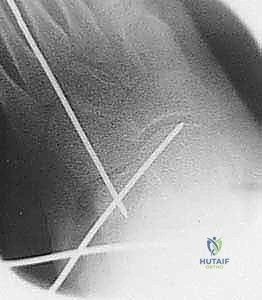

3. القطع العظمي (The Osteotomy)

باستخدام منشار جراحي دقيق، يتم إجراء قطع في عظم الكعب (Calcaneus). يتم تحديد مكان القطع بدقة بالغة، عادةً على بعد حوالي 1.5 سم خلف المفصل العقبي النردي (Calcaneocuboid Joint). يحرص الدكتور هطيف على الحفاظ على القشرة العظمية الداخلية (Medial Cortex) سليمة لتكون بمثابة مفصلة (Hinge) تمنع عدم استقرار العظم.

5. التثبيت الداخلي (Internal Fixation)

لضمان عدم تحرك الطعم العظمي أثناء فترة الالتئام، يتم تثبيت التكوين الجديد. يستخدم الدكتور هطيف أحدث تقنيات التثبيت، والتي قد تشمل شريحة معدنية صغيرة مع مسامير (Plate and Screws)، أو مسامير معدنية تمر عبر العظم، أو أسلاك كيرشنر (K-wires)، وذلك لضمان أقصى درجات الثبات الميكانيكي.

يتم التأكد من صحة التثبيت والتصحيح باستخدام جهاز الأشعة السينية المباشر (C-arm Fluoroscopy) داخل غرفة العمليات قبل إغلاق الجرح.